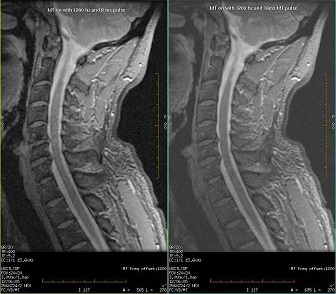

Figure 1. MT C-spine with 1200 Hz offset, 8 msec (left) and 1200 Hz offset , 16 msec (right)